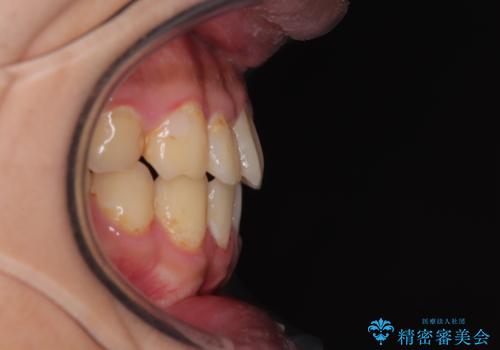

- 前歯のデコボコとクロスバイトを気にして来院された患者様です。

気になっていたクロスバイトは速やかに改善され、1年間で治療を終えることができました。